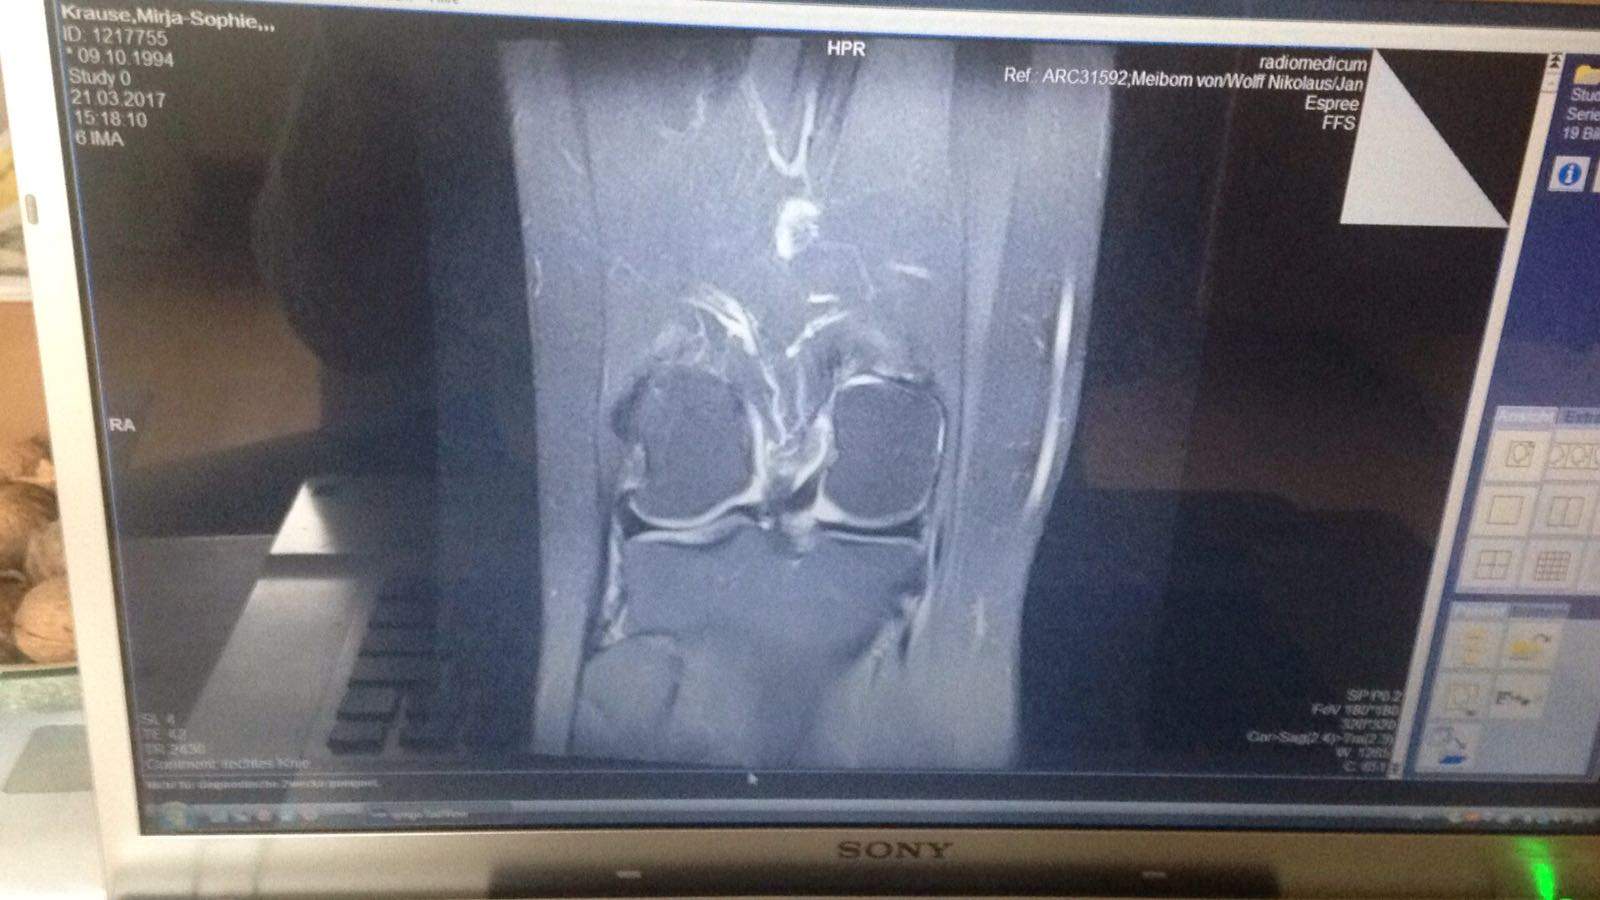

Grad 1: es zeigen sich leichte oberflächliche Veränderungen oder eine Erweichung. Grad 2: der Knorpel ist an der beschriebenen Stelle schon deutlich beschädigt, die Tiefe des Knorpelschadens ist aber noch <50% der Knorpeldicke. Grad 3: > 50%. Grad 4: Knochenglatze, d.h. der Knorpel zeigt einen Schaden, der bis auf den darunterliegenden.

Einteilung. Den Knorpelschaden teilt man in vier Schweregrade ein ( Klassifikation nach Outerbridge): Stadium 1: leichte oberflächliche Auffaserung. Stadium 2: halbschichtige Einrisse und breite Oberflächenauffaserungen. Stadium 3: tiefer, bis zum Knochen reichender Defekt mit starker Auffaserung, mechanisch nicht mehr tragfähig.